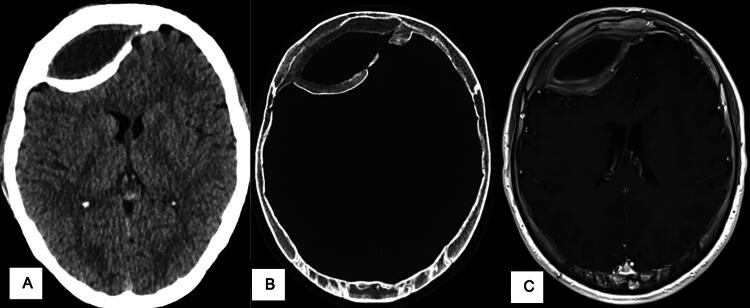

The presence of a calcified or ossified chronic cranial epidural hematoma (EDH) is rare and has been described in only a few case reports in the literature. Consequently, clear treatment strategies remain elusive and may entail conservative and surgical approaches. In this study, we performed a systematic review of reported cases to evaluate the clinical course and treatment options for these patients. A comprehensive systematic search of two databases was performed, and information on patient characteristics, symptomatology, and treatment was extracted from eligible articles. A total of 56 cases were included in our analyses. Forty patients were male, 16 were female, with an average age of 21.38 years at the time of diagnosis. Assumed etiology was previous trauma in 35 cases, previous cranial surgery in 17 patients, and birth trauma and epidural bleeding after the utilization of the Mayfield clamp in 1 case each. The origin remained unclear in two cases. The time between trauma or surgery and diagnostics ranged between one and a half weeks and 50 years, with a median of 4 years (SD 9.8 years). The symptoms were very heterogeneous, ranging from acute neurological deterioration to chronic symptoms. In 15 cases, patients were asymptomatic, and cranial imaging was performed as part of a new trauma or a screening for other disease. Forty-one patients received surgical treatment by craniotomy and hematoma evacuation, and 13 patients were treated conservatively. In two cases, the liquid hematoma portion was aspirated through a burr hole. The localization of calcified or ossified EDH was mainly supratentorial. Young male patients most commonly present with calcified or ossified EDH after trauma, according to the epidemiological trend of acute EDH. Clinical presentation varies from asymptomatic to severe neurological deficits and signs of increased intracranial pressure. There is no standardized treatment; decisions must be made on an individual basis.

Abstract Image